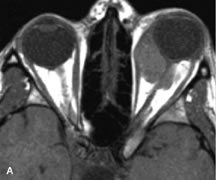

On MRI, uveal melanomas have a typical appearance that helps to differentiate them from other primary and secondary intraocular tumors as well as choroidal detachments. Pigmented melanomas are hyperintense on Tl-weighted images, hypointense on T2-weighted studies, and hyperintense on proton density–weighted examinations (Fig. 24).30,31,50,80–82 These signal characteristics have been attributed to the paramagnetic properties of melanin because of stable free radicals that shorten the T1 and T2 relaxation times. Moderate enhancement is seen on postgadolinium T2-weighted images. Gadolinium-enhanced T1-weighted images are particularly sensitive in detecting choroidal melanomas.83 MRI may be less sensitive in detecting extrascleral extension of tumor than echography performed by an experienced ultrasonographer.84

Fig. 24. A. T1- and (B) T2-weighted MR scans demonstrate a small nodular intraocular mass (arrows) that is very hyperintense on the T1-weighted scan and hypointense on the T2-weighted image. This signal intensity pattern is due to the presence of free radicals within melanin granules. C and D. Postcontrast fat-suppressed T1-weighted scans demonstrate homogeneous intense enhancement of the lesion and no evidence of seleral penetration or optic nerve invasion.